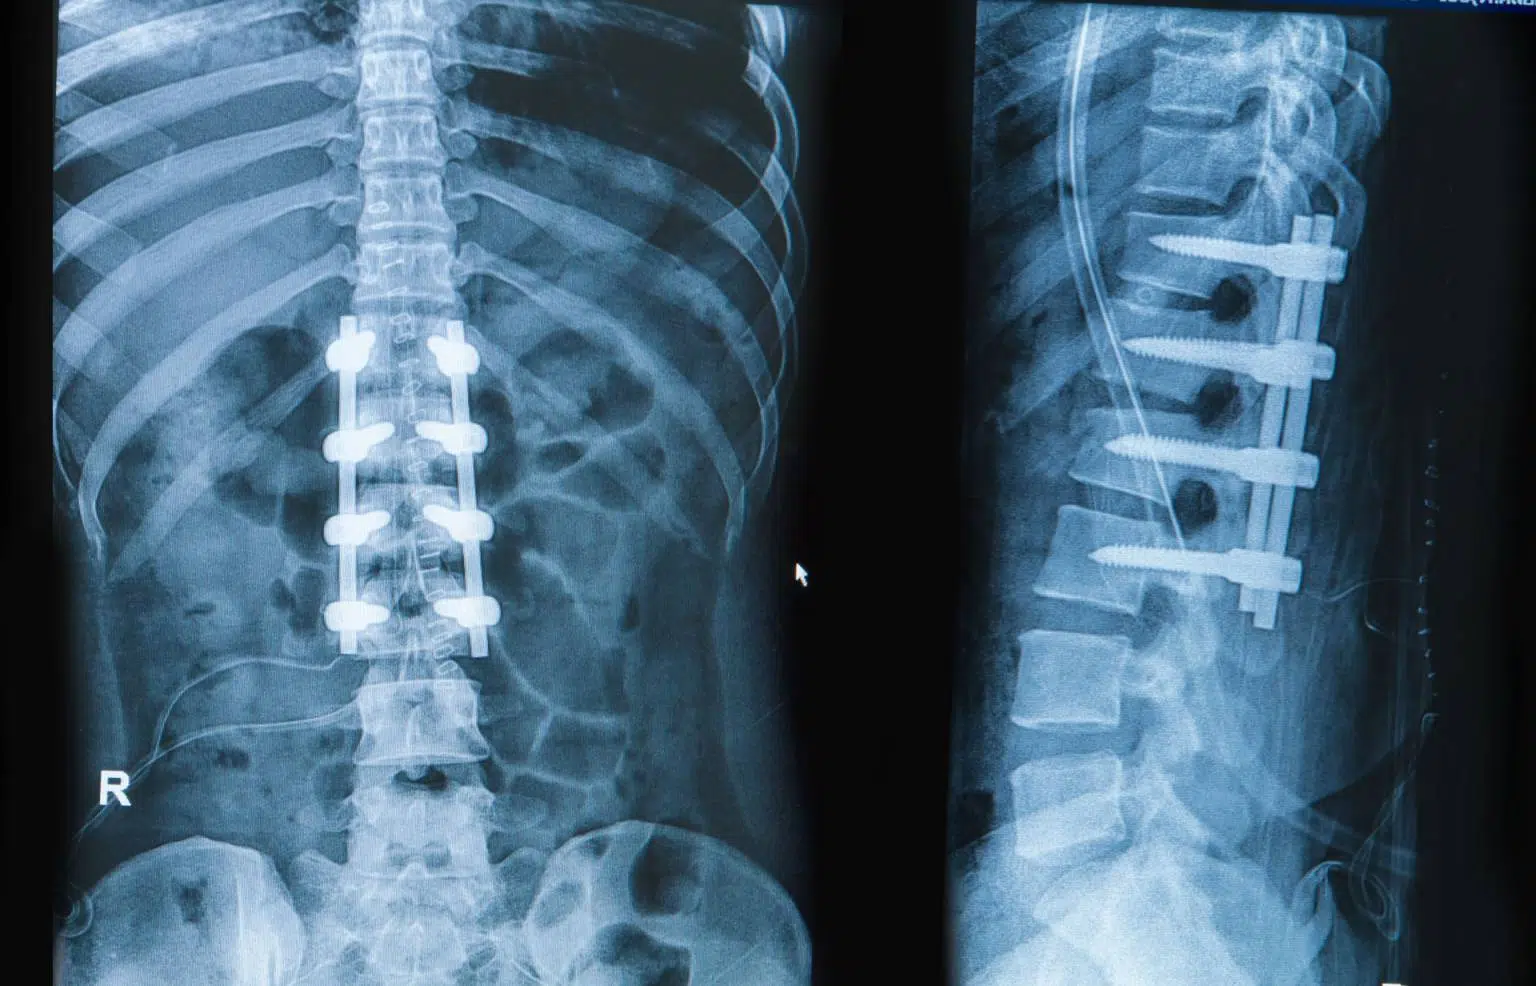

Spinal Fusion

Spinal Fusion is a modern approach that combines the stability of traditional spinal fusion with the minimally invasive benefits of spinal endoscopy. This technique allows us to join two or more vertebrae through small incisions, reducing muscle disruption and scarring. It’s typically recommended for conditions like spinal instability, deformities, or chronic pain where controlling motion is essential. Patients can expect less post-op discomfort and a quicker recovery compared to conventional open fusion.

Ideal for:

- Revision Spinal Surgery

- Leg pain or sciatica

- Spinal narrowing (stenosis)

- Deformity

- Spondylolisthesis

Benefits:

- Tiny incision, less scarring

- Same-day discharge for most patients

- Faster return to work and activity

Minimally Invasive Fixation

A technique that stabilises the spine using screws and rods inserted through small incisions, guided by imaging. It avoids traditional open surgery by using tubular retractors and navigation tools to reduce trauma to surrounding tissues.

- Spinal fractures (trauma or osteoporosis)

- Instability from tumours or degenerative conditions

- Patients who are elderly or medically high-risk

- Shorter recovery time

- Less blood loss and muscle damage

- Smaller scars and reduced infection risk

- Faster return to mobility